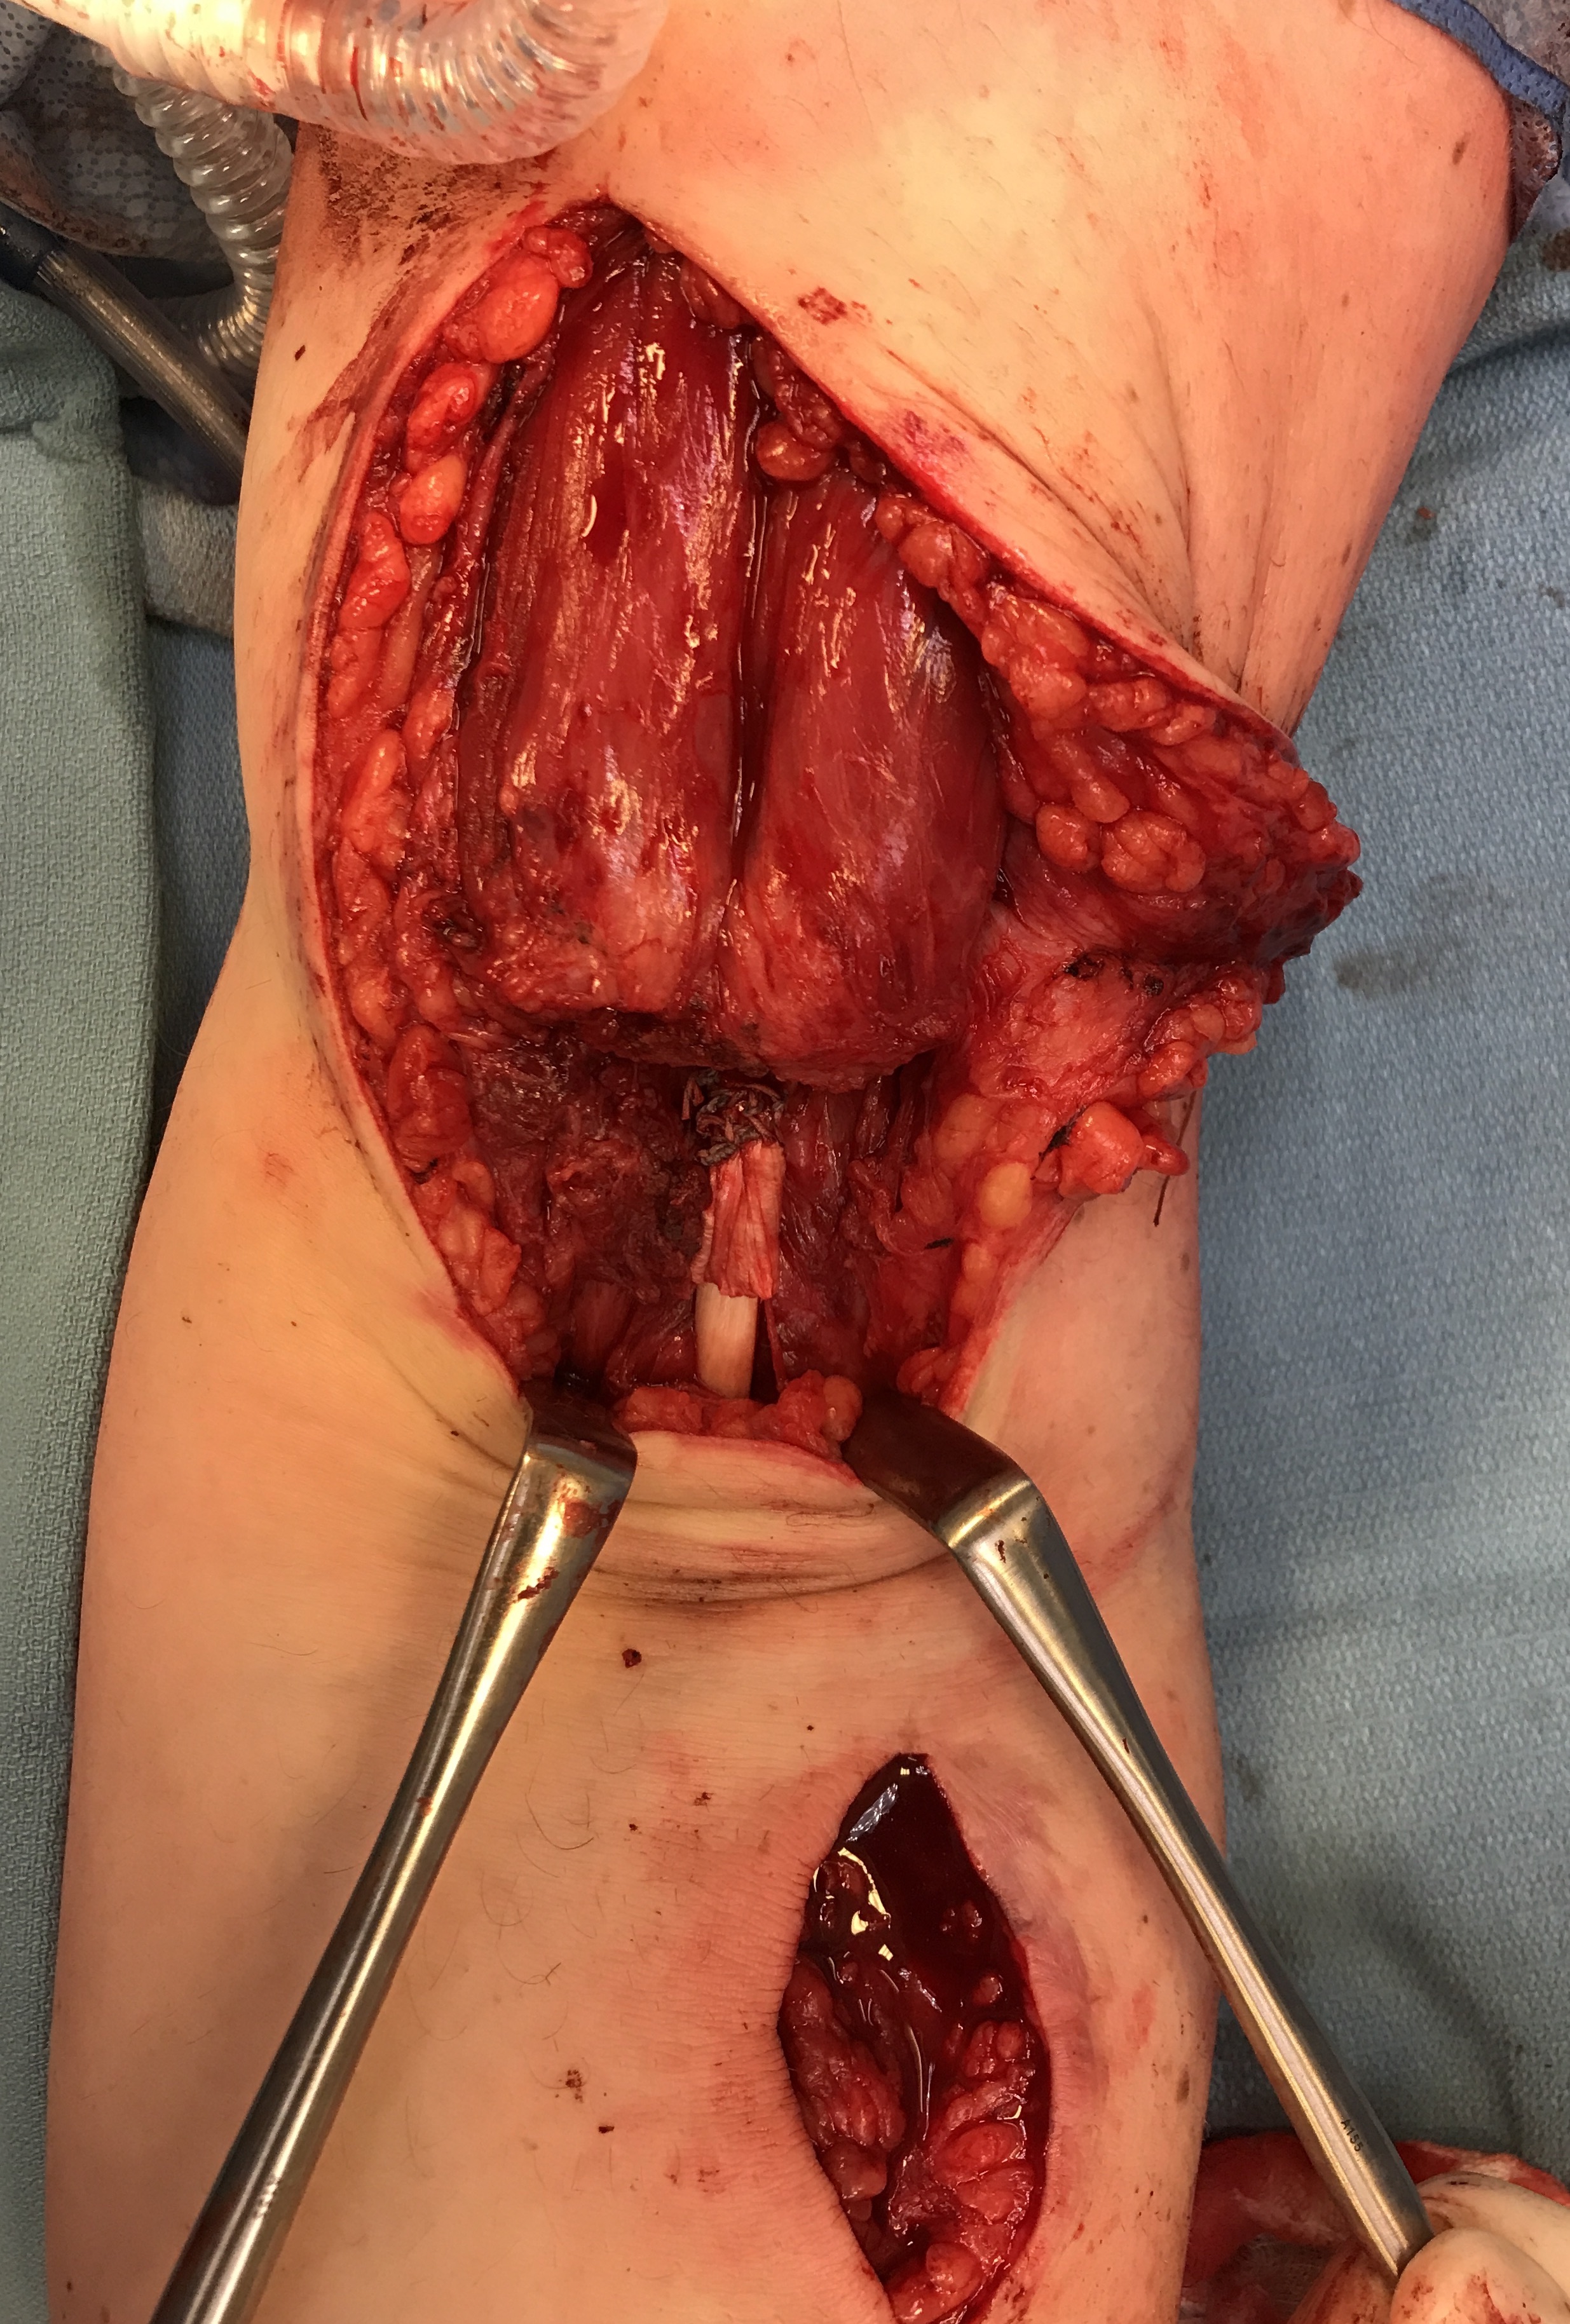

Distal Biceps Repair IncisionDistal Biceps Tendon with Endobutton

Tunnel distal biceps tendon to radial tuberosity

Distal Biceps Endobutton RepairDistal Biceps Endobutton RepairDistal Biceps Repair Final